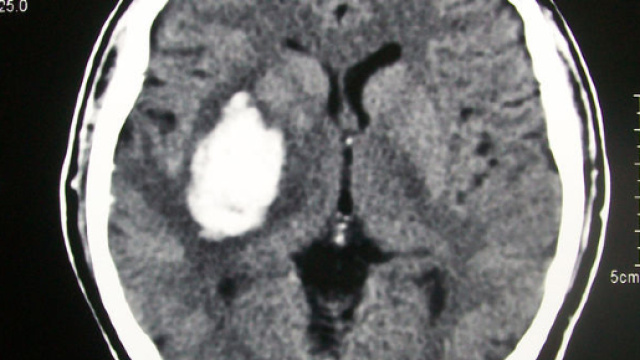

Una signora aveva deciso di rivolgersi al nosocomio partenopeo per effettuare degli accertamenti. Da tempo era tormentata dal mal di testa e come accade in questi casi, per stabilire l'origine della cefalea, l'esame più efficace è quello della tac, fatta anche con una certa urgenza. Chi è stato sottoposto ad un esame di questo tipo sa bene che lo staff si cura di fare in modo che il paziente si collochi nella posizione giusta e soprattutto che non entrino oggetti estranei. Sembrava davvero essere stato tutto fatto a regola d'arte, se non fosse che al momento dell'inizio dell'esame sullo schermo è stato possibile notare come la paziente fosse riuscita ad accedere nel macchinario per la tomografia computerizzata con un telefono cellulare.

La cosa fa anche sorridere, ma poteva rappresentare davvero un rischio inenarrabile per la signora. Il fatto diventa grottesco se si considera che, mentre i tecnici si accorgevano di quanto fosse accaduto, pare che la protagonista della vicenda sia stata rapidissima nel rispondere ad una chiamata. Inutile sottolineare come gli addetti abbiano immediatamente provveduto a sospendere l'esame per evitare che quel corpo estraneo potesse generare conseguenze sgradite. Lascia, inoltre, basiti quella che è stata la spiegazione della signora che si è limitata a porre il rilievo il fatto che il non aver lasciato all'esterno il telefono fosse stata una semplice dimenticanza.

La macchina ovviamente ha provveduto a registrare le fasi in cui la donna ha risposto al telefono e, considerato anche il fatto che sono stati scongiurati pericoli, è stato possibile rendere pubblica la singolare immagine. Una sorta di monito attraverso cui probabilmente da parte dell'Ospedale c'è stata voglia di raccontare al mondo quanto una cosa così singolare, a tratti divertente, avesse in realtà potuto portare a conseguenze ben peggiori. A rendere ancor più dolce la vicenda c'è la notizia che l'esame è stato poi ripetuto e la signora ha potuto avere contezza del fatto che nessuna patologia neurologica fosse la causa di quel mal di testa. Sarebbe, invece, forse opportuno ragionare sulla sua eventuale incapacità di stare lontano dal suo telefono, forse una dipendenza che condivide con milioni di persone. O forse si è trattato davvero di casualità.